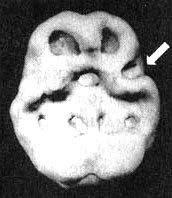

Мозг Стивена. Суицидальные мысли

Иллюстрация к книге — Измените свой мозг - изменится и жизнь! [i_082.jpg]

Трехмерное изображение, вид снизу — активный мозг.

Обратите внимание на выраженно повышенную активность в левой височной доле и в поясной системе (стрелки).